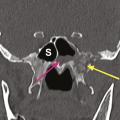

Le diagnostic d’aspergillose pulmonaire doit également faire pratiquer une imagerie sinusienne dans le bilan d’extension. L’examen d’imagerie de première intention est le scanner, qui met en évidence un épaississement muqueux sinusien associé à une ostéolyse de contact (fig. 1), qui peut cependant être inconstante dans les stades précoces de la maladie.

Le bilan comprend une imagerie par résonance magnétique (IRM) pour l’évaluation des tissus mous et une angio-tomodensitométrie (angio-TDM) pour rechercher une atteinte vasculaire. L’évolution de l’infection est en effet marquée par un angiotropisme. L’envahissement du sinus caverneux est une complication fréquente qui peut aboutir à un anévrisme mycotique de la carotide interne. L’envahissement de l’artère sphénopalatine peut entraîner l’invasion de la fosse infratemporale. L’extension depuis l’ethmoïde peut se faire vers l’orbite – induisant baisse d’acuité visuelle, ophtalmoplégie et exophtalmie – et/ou vers le compartiment intra-crânien (fig. 2).